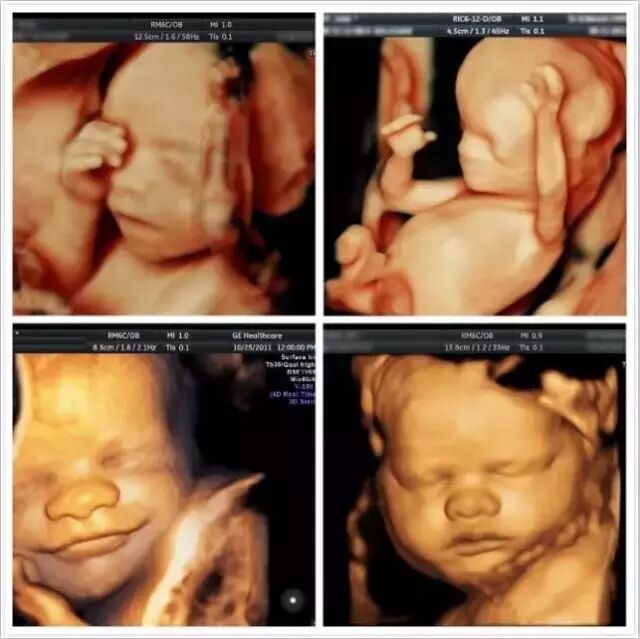

整个孕期有5次以上产检,通过产检可以筛查出高危孕产妇,及时诊断和治疗,减少患儿出生。如在孕期24周左右的四维彩超,能直观立体显示器官的结构与动态,对筛查缺陷十分有意义。

四维彩超的优势

胎儿四维超声检查技术,也就是四维成像技术,是目前先进的超声诊断技术,能直观、立体显示人体器官的三维结构及动态、实时地观察立体结构,筛查发育情况,广泛运用于对胎儿进行超声检查。在立体观察宫内胎儿发育情况的同时,还能清晰显示胎儿在宫内的动态。

“我约了一个人,在十个月之后见面,我暂时不知道TA的样子,但我想只要一见面就不会忘记。”如今随着四维彩超愈发普及,再也不用苦苦等待漫长的十个月,四维彩超可自动为胎儿进行“深宫”照相及生成动态图像,让准爸妈能清新一睹宝宝“宫”内举动和乖巧秀容。